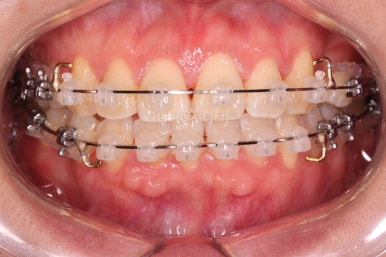

브라켓을 부착합니다.

이번 환자분이 선택하신 장치는 데이몬 클리어라고 하는 자가결찰 세라믹 장치인데요.

일반적으로 흔히 아시는 클리피씨 장치에 비해서 철사를 잡아주는 뚜껑까지 세라믹으로 되어 있어서 아마도 현존하는 세라믹 장치 중에서는 가장 심미적인 장치라고 볼 수 있습니다.

대신, 세라믹으로 되어 있다보니 강도 때문에 부피는 조금 더 커진다는 단점은 있긴 합니다.

장치 부착 직후의 웃는 모습과 입이 좀 더 나오는 양상을 참고해 주시고요.